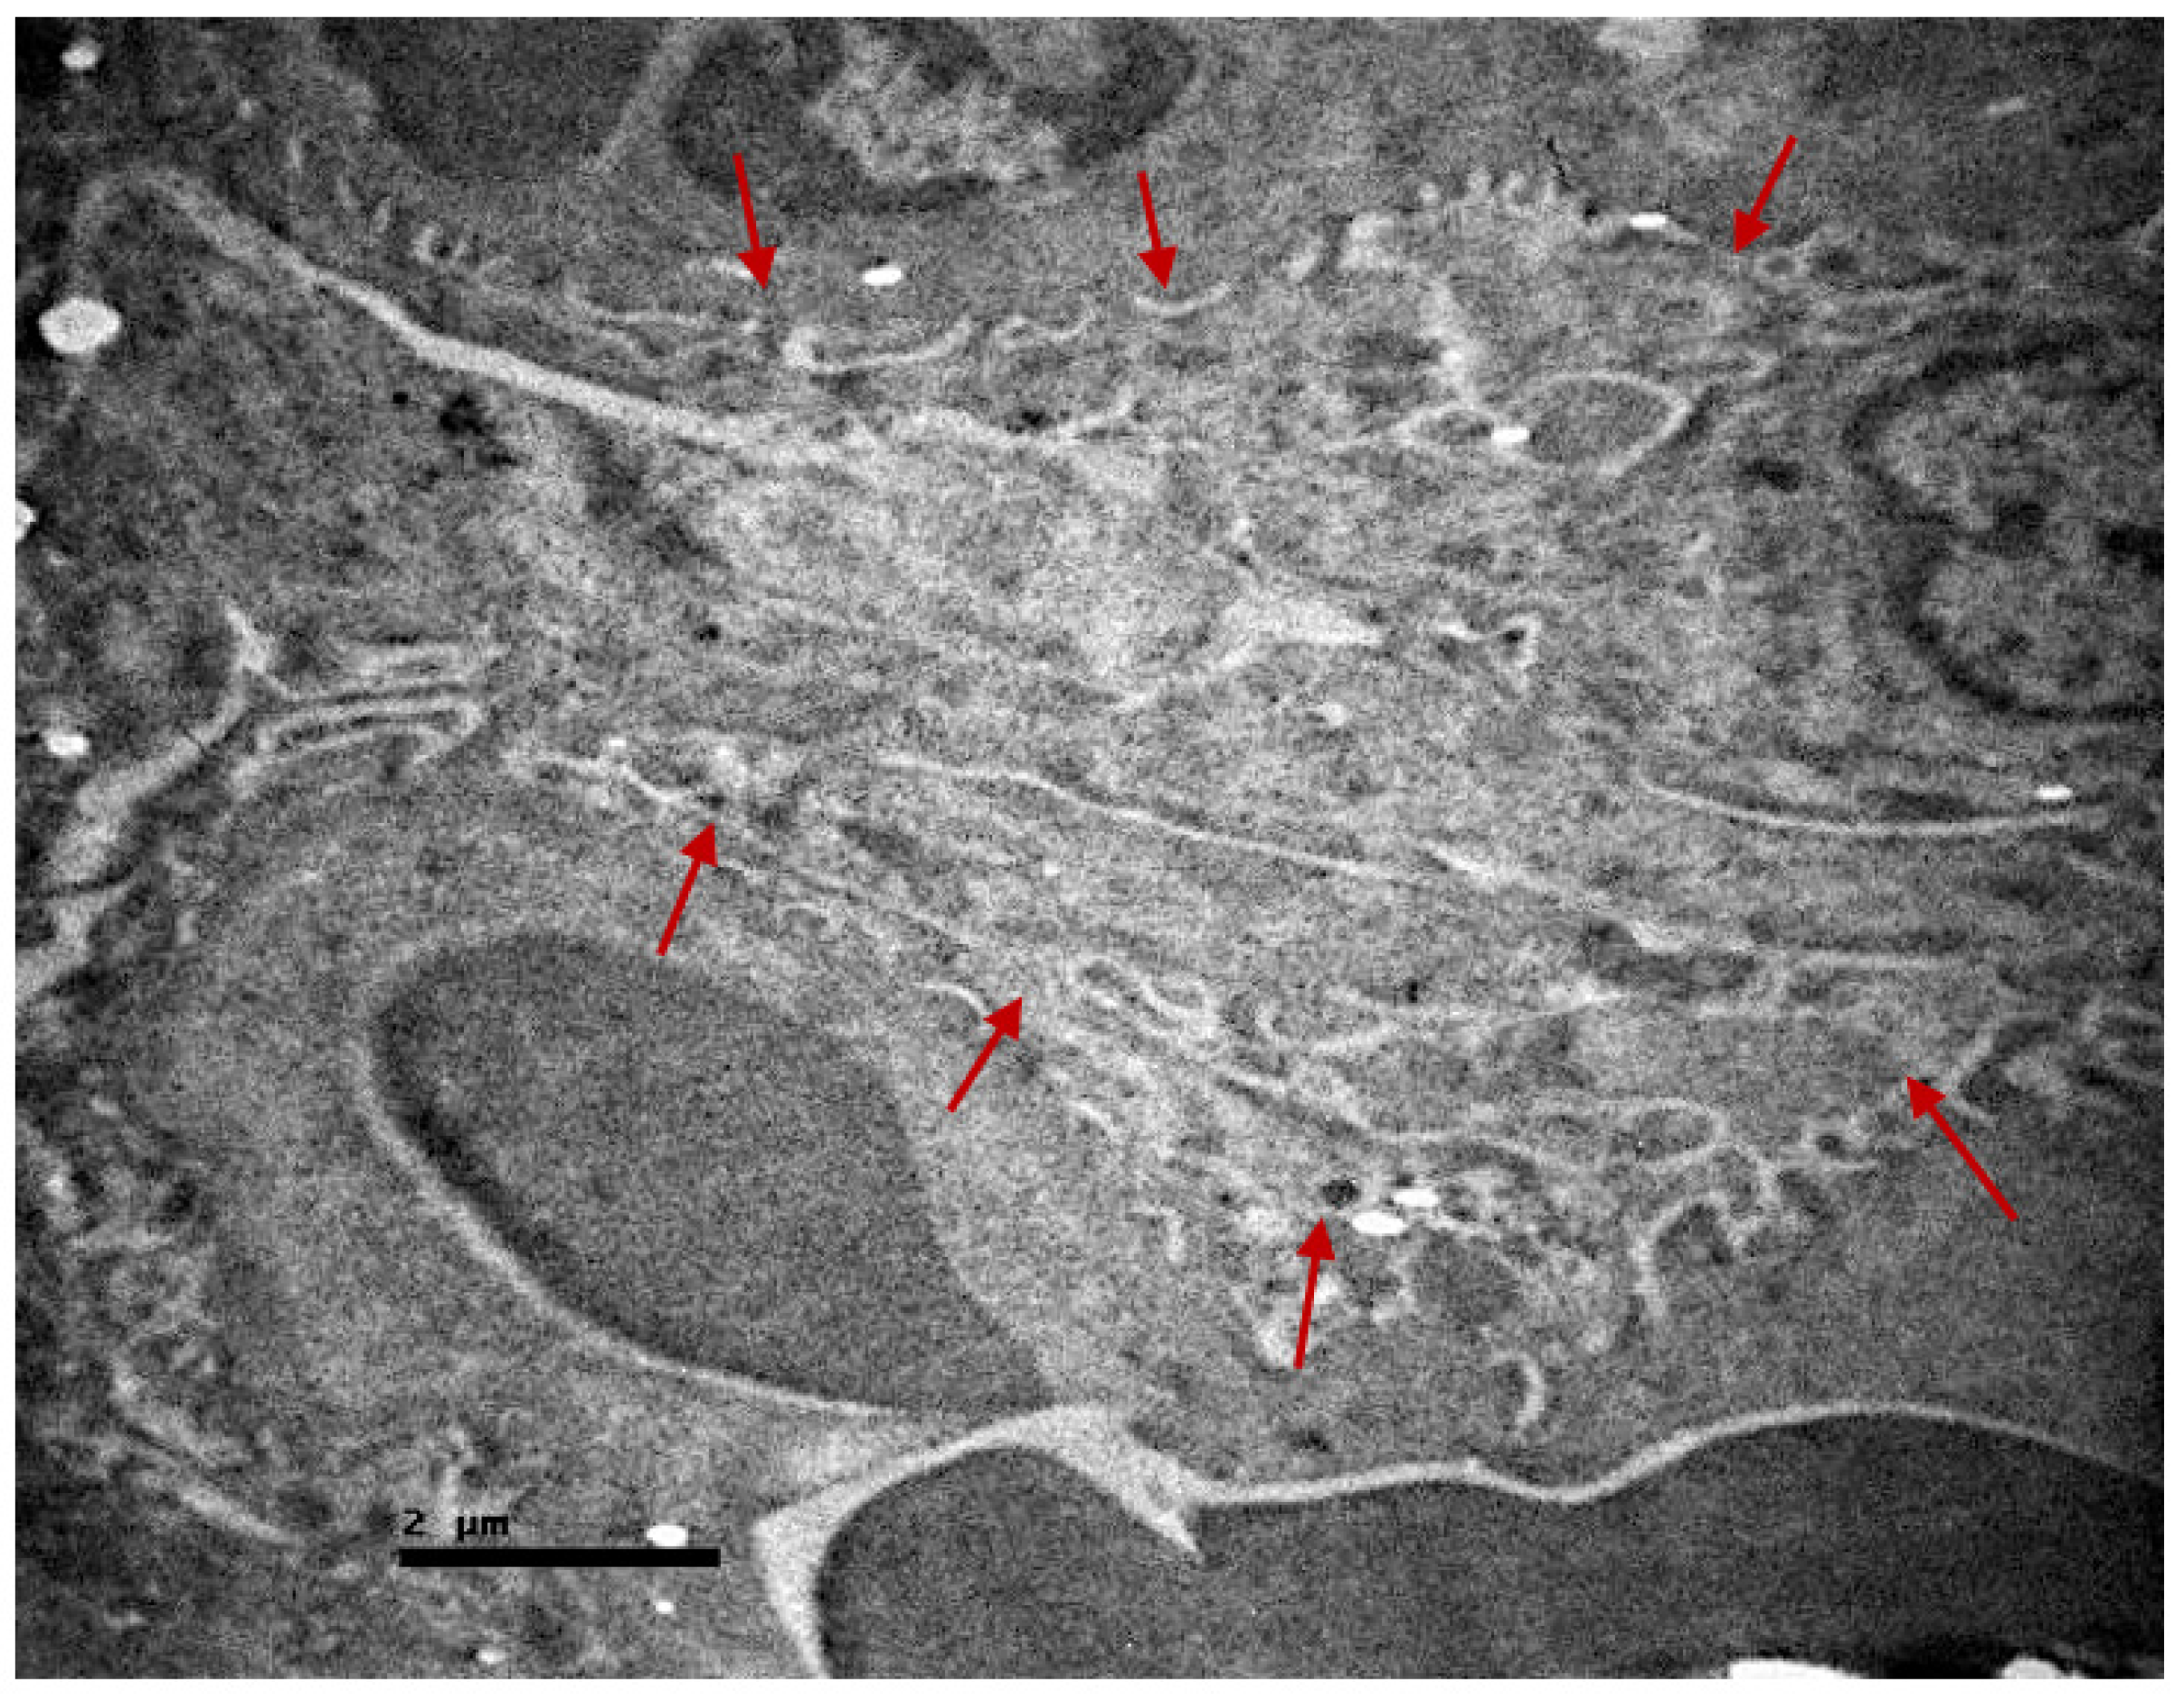

2.2. Electron Microscopic Evaluation